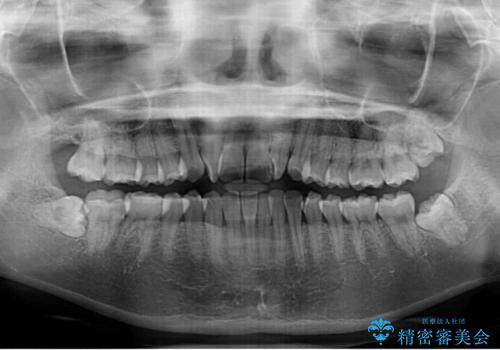

- 上下前歯のねじれを気にして来院された患者様です。

ワイヤー矯正でもマウスピース矯正でも対応可能でしたが、マウスピース矯正の自己管理が面倒であること、上顎前歯の捻転が著しいことから、ワイヤー矯正での治療を希望されました。

- 症状により、抜歯が必要な場合があります